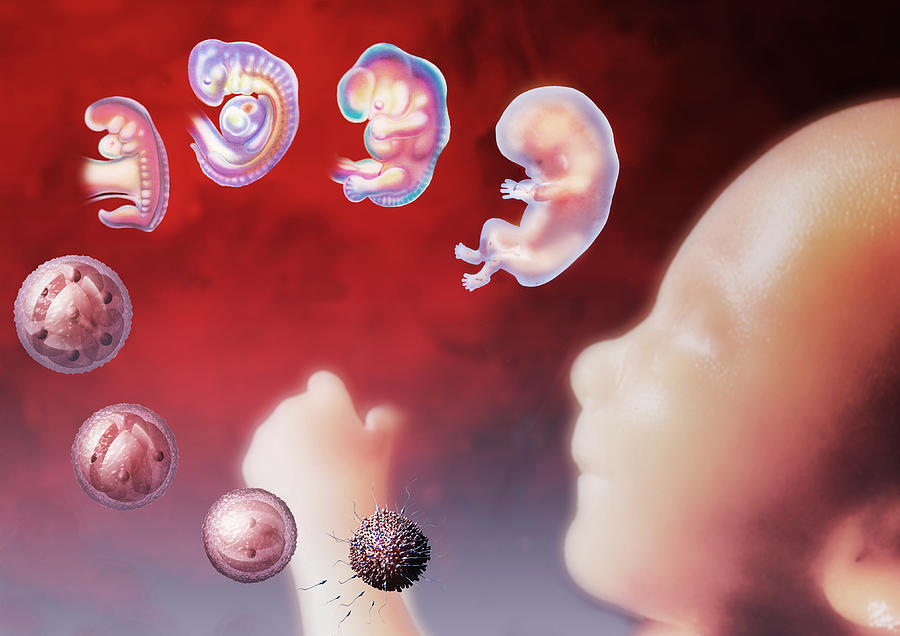

Загадочные образы животных в утробе матери